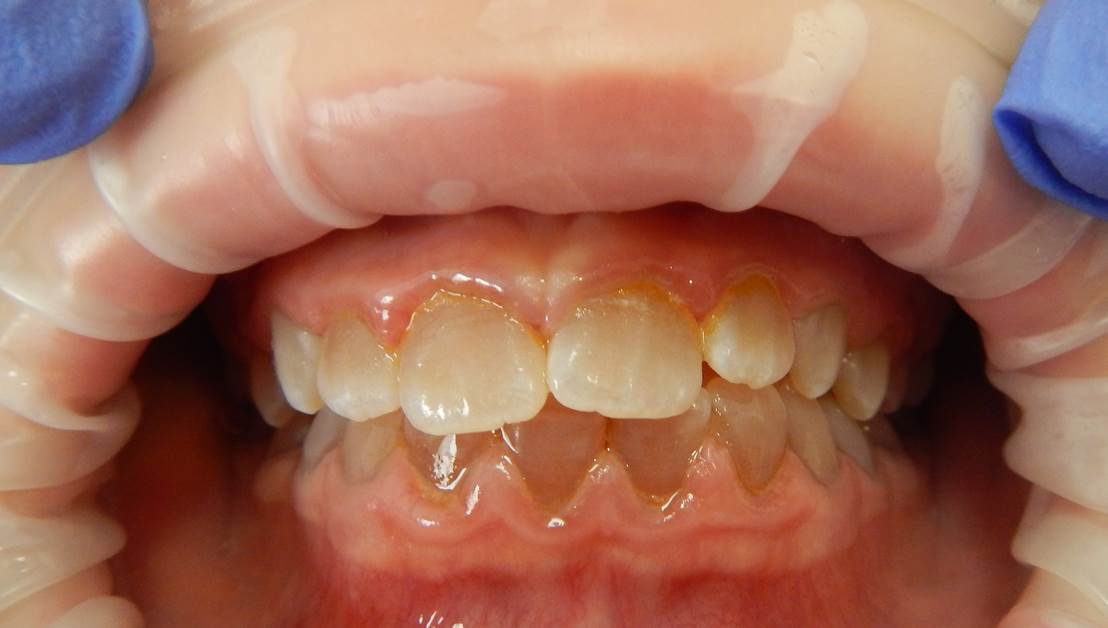

Photographie intrabuccale